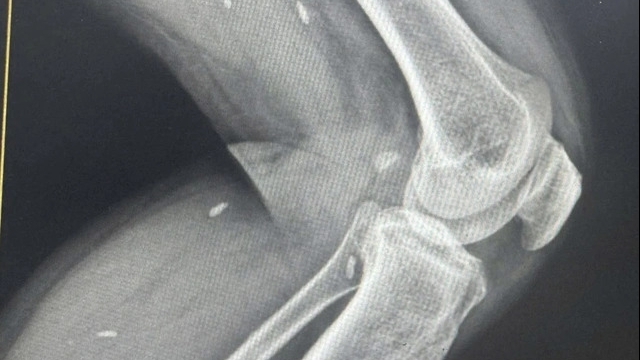

Kết quả CT - Scan ghi nhận hai dị vật dài khoảng 5 - 6 cm từ hốc mũi phải xuyên thành trong và sau xoang hàm phải và vùng cơ chân bướm - sàn sọ phải.

Bệnh nhân được các bác sĩ chẩn đoán dị vật hốc mũi bỏ quên bên phải xuyên xoang hàm, vùng cơ chân bướm phải và được chỉ định thực hiện các xét nghiệm cần thiết để phẫu thuật nội soi lấy dị vật.

Kíp can thiệp do BS.CKII Nguyễn Thanh Hải - Phó Trưởng khoa Mũi Xoang phụ trách, đã phẫu thuật nội soi lấy được dị vật là 2 đoạn đũa dài khoảng 5 – 6 cm. Sau đó, bệnh nhân được tiếp tục được điều trị nội khoa để ngừa nhiễm trùng.